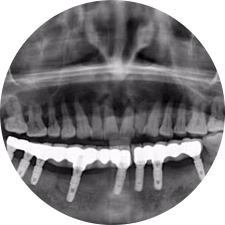

口腔種植是將人工牙根通過手術植入牙骨內,獲得牙槽骨牢固的支持,通過特殊的裝置和方式連接牙修復體,獲得與天然牙功能、結構以及美觀相似的效果。

術前患者CBCT口掃1:1三維重建,模擬手術過程及預測術后治療效果,確定每顆植體植入的適合的種植位點、深度及角度,有效避免損傷頜骨重要解剖結構,提高手術準確度與安全性。

惟德口腔種植體系是以患者感受為中心,取代傳統(tǒng)種植牙手術需要翻瓣、打孔、縫合,術前、術中、術后的繁復流程,采用3D導航微創(chuàng)準確種植技術,通過數字化CAD/CAM掃描技術獲得缺牙患者口腔數據,以數據為基礎重建口腔模型進行模擬種植。

術前將患者口內的CBCT數據及咬合關系上傳到計算機中,建立1:1三維重建,模擬手術過程及預測術后治療效果,找出較佳種植位點、深度及角度,獲取實際種植體在頜骨內的具體三維位置,有效避免損傷頜骨重要解剖結構,大大降低手術風險,提升種植成功率。